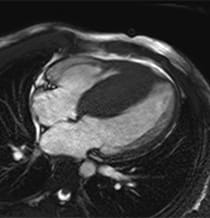

Image of a heart with hypertrophic cardiomyopathy.

- Cardiac MRI – A contrast agent is used with a magnet and radio waves to create an image of your heart. This imaging can better show your provider how thick your heart is and if there is any fibrosis or scarring that has occurred. This information can better guide your treatment plan.